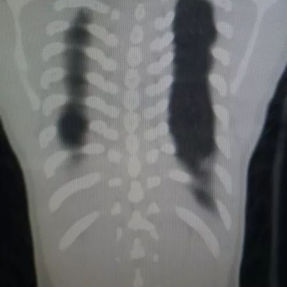

The patient’s anterior chest wall exhibits a prominent depression deformity,characterized by a horizontal groove that affects both sides of the anterior chest wall. There is a surgical scar along the midline and one on the left side, with two scars visible on the right side of the chest wall. A 4x4 cm mass is located on the left chest wall, characterized by darkened skin and noticeable fluctuation upon palpation. The mass extends deep into the intercostal space. Mild scoliosis is also observed. The patient was ultimately diagnosed with grooved chest.

2. Improper bar Placement and Positioning: Preoperative imaging reveals that the bar was positioned along the upper edge of the groove-like depression and was placed at an angle.For optimal support and effective correction of the depressed bony structure, the bar should have been positioned at the base of the depression.